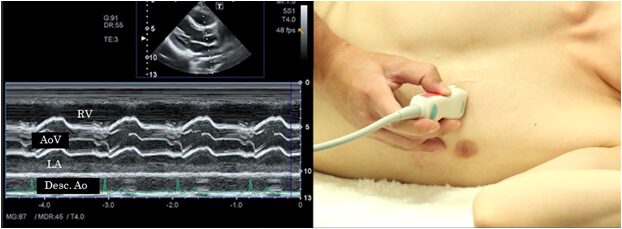

Aortic valve

In M-mode at the aortic valve level, record the parts that ultrasound beam passes through the right ventricular outflow tract, the cusp of the aortic valve and left atrium. When recording the image, confirm that the beam does not enter obliquely using both the long and short axis views. This view is suitable for the observation of systolic semi-closure of the aortic valve seen in hypertrophic cardiomyopathy.